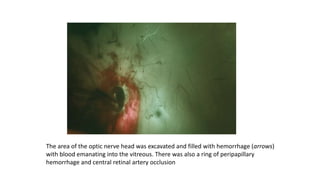

The area of the optic nerve head was excavated and filled with hemorrhage (arrows)

with blood emanating into the vitreous. There was also a ring of peripapillary

hemorrhage and central retinal artery occlusion